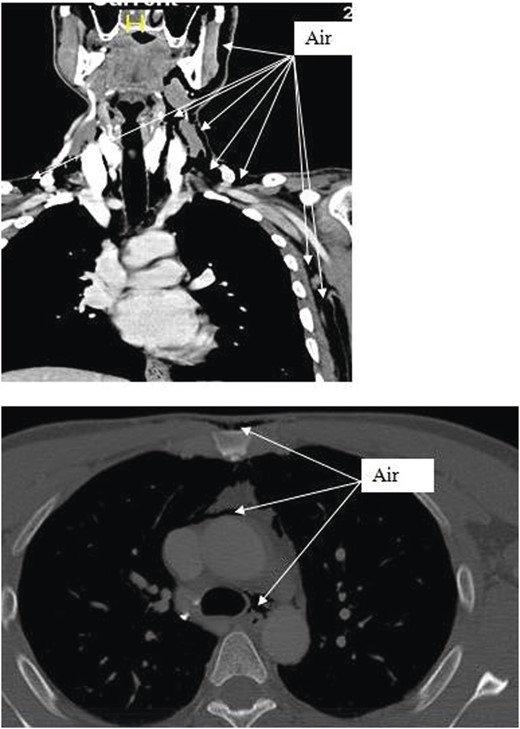

Chest X-ray and head, neck and chest computed tomography (CT) confirmed the diagnosis and extension of PM (Figs 1–3). CT revealed fracture of the floor of left orbit with soft tissue, fat herniation into left maxillary sinus roof, left orbital emphysema with no muscular entrapment. Gas was observed in periorbital tissues, left temporal scalp, infratemporal fossa, left parapharyngeal space and left cheek. Moreover, tissue planes in the neck revealed the presence of air particularly around the carotid vessels, in the posterior triangle and superior mediastinum (PM) around the thymus, trachea (middle), left side of the aorta and anterior to the sternum. However, on auscultation, lungs were clear with and the laryngeal passages and trachea looked normal.

CT scan shows the extension of air from the face, neck and chest.